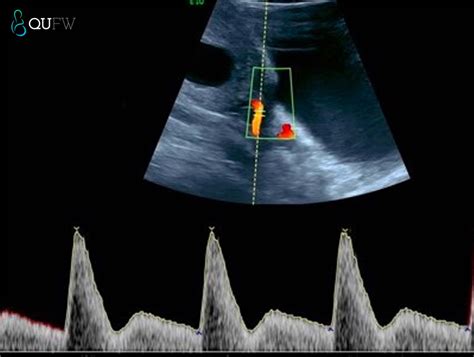

At its core, the Nuchal Translucency Screening is a specialized ultrasound scan that measures the clear space—the translucent area—at the back of your baby’s neck. During early development, all babies have some fluid in this area. However, research has shown that if this space is larger than average, it may be an early indicator of certain genetic conditions, such as Down syndrome (trisomy 21), Edwards syndrome (trisomy 18), or structural heart defects.

During the appointment, a sonographer will use an ultrasound transducer on your abdomen or, less commonly, transvaginally, to obtain a clear image of the fetus. The process is generally quick, painless, and completely safe for both the parent and the baby. The sonographer carefully measures the thickness of the fluid collection at the nape of the neck while the baby is lying in a neutral position.

💡 Note: The accuracy of the Nuchal Translucency measurement relies heavily on the baby's position; if the baby is curled up or moving too much, the technician may need a little extra time to get the perfect angle.